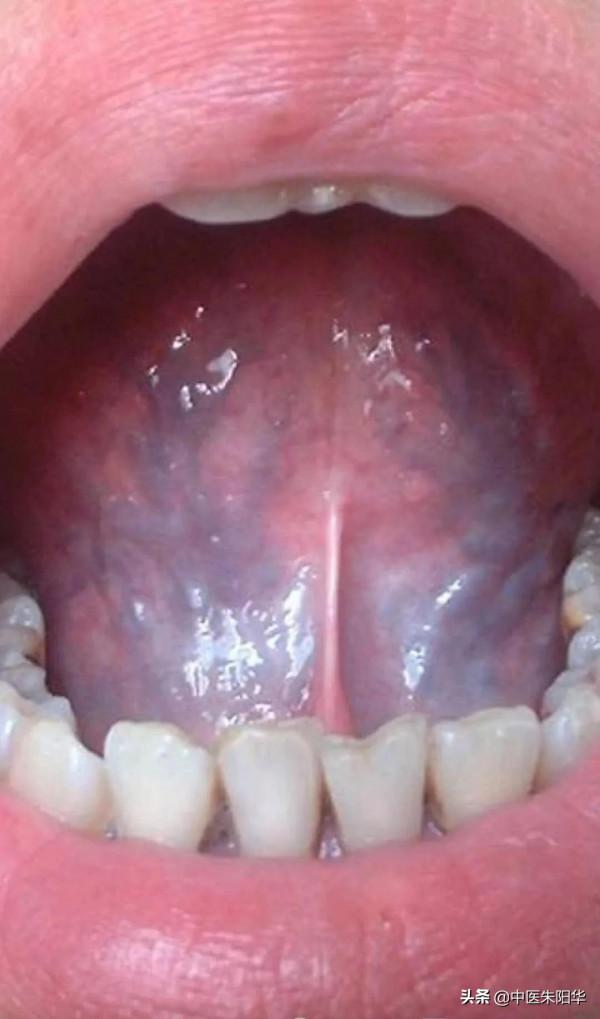

快看你的舌苔是不是這樣?

氣沒有力量推動血液運行了,血液就會停留,比如有些人有心臟無力、心臟停跳,都會讓血液執行無力,這個就得調整心臟。《傷寒論》中的炙甘草湯,就是專門治療心悸動、脈結代的藥方,所謂的脈結代,其實就是心氣虛損,不能推動血液運行了,這種人不但舌底有鬱絡,整個舌面也都發青,炙甘草湯裡面有人參,人參可以補氣,可以增加血行的力量。